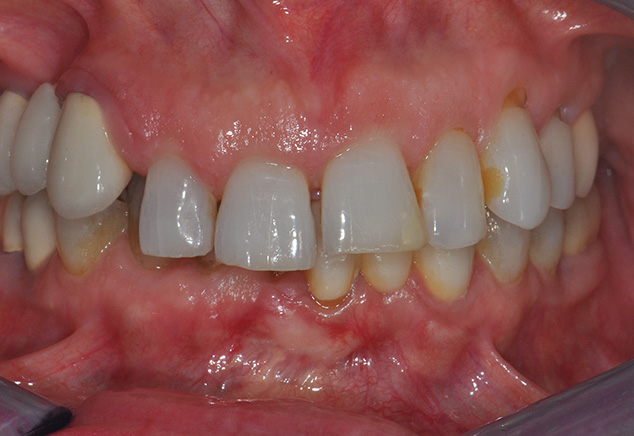

The patient presented to our offices as a 65 year-old non-smoking female (ASA 3: Illnesses under treatment: anxiety/depression, osteoarthritis, fibromyalgia, hypothyroid and history of myofacial pain dysfunction) to our office (Fig. 1, Fig. 2, Fig. 3). There was a history of TMJ issues (ie. clicking and pain with her right side TM joint) which presently is under control and pain-free. Her chief complaint was to improve her esthetics and comfort with desire for a permanent and quick solution to replace her failing dentition. She also desires a reduction of her maxillary anterior gummy smile in the final prosthesis. She arrived to our office for a third surgical consult for an immediate load maxillary and mandibular hybrid restoration using the Straumann® Pro Arch treatment concept (tilting of the distal implants to avoid anatomic structures of the maxillary sinus, mandibular mental foramina). This treatment concept reduced the need for additional surgeries and number of implants needed to provide a fixed hybrid restoration with a first molar occlusion. A medium to high lip line was noted upon a wide smile with a bi-level plan of occlusion. Also noted was supraeruption of her maxillary and mandibular anterior teeth (#7-10 and #25-27) creating a deep bite of 6mm (Fig 2). A Class I canine relationship relationship was recorded with 6 mm overjet & 6 mm overbite. Due to her medication-related dry mouth issue, generalized recurrent caries were noted. Periodontal probing depths ranged generally 4-7mm in the maxillary jaw and 4 to 6mm in the mandibular jaw with moderate to severe marginal gingival bleeding upon probing in both jaws. Tooth #6 was noted to have a vertical fracture clinically. There was generalized heavy fremitus in her maxillary teeth and mobilities ranging 2-3 degrees on the following teeth: #3, 7 thru 13, 20-26 and 29. Her compliance profile was good with her previous dentists, however, she states as always having "issues with my gums." The tentative treatment plan that was discussed at the initial visit, with the patient and her husband, included the following: